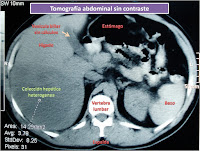

Un paciente varón de 47 años, acude a la consulta por fiebre, dolor abdominal y anemia. El paciente, refiere baja de peso de 10 kilogramos en seis meses y se muestra pálido, con taquicardia (palpitaciones), muestra caries de manera moderada, dolor al palpar el abdomen y masa palpable a ese nivel. Se le solicita una tomografía abdominal (Fig. N° 1 y Fig. N° 2 ) la cual muestra una masa de más o menos 20 cm de diámetro (el diámetro de una maceta mediana), de aspecto heterogéneo lo cual sugiere absceso hepático. Lo que no cuadraba era que al inyectar contraste (una sustancia que hace que el territorio hepático se incremente en intensidad imagenológica) y tomar la tomografía, se veía aumento de contraste al interior del absceso en forma de tabiques lo cual no es frecuente en abscesos hepáticos, sino en neoplasias.